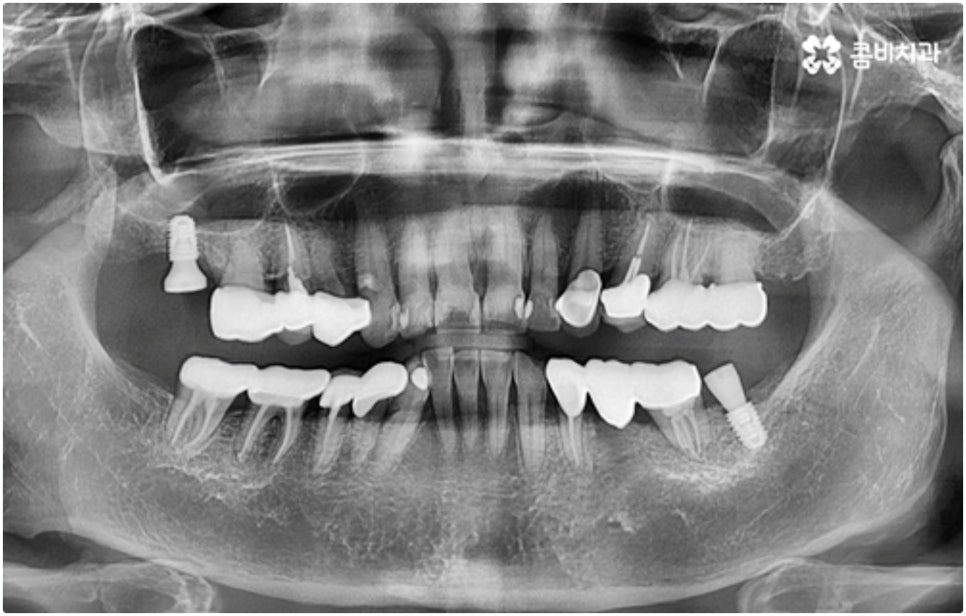

식립 성공률 및 지속적인 안정성을 높이기 위해서는 초기 고정이 잘 이루어져야 하는데 만약에 식립 바탕이 되는 잇몸뼈의 상황이 좋지 않다면 이와 관련된 치료를 먼저 해 줘야 하는 거예요. 예를 들어 치주 질환이 심하다면 이를 깨끗하게 치료해 주는 것이 우선시 되어야 하고, 잇몸뼈의 높이나 밀도 등이 부족한 경우에는 뼈이식 과정을 통해 이를 먼저 보충해 줄 필요가 있어요. 또한 윗어금니가 빠진지 오랜 시간이 지나 이미 골흡수가 일어나고 상악동이 많이 내려와 있다면 상악동 거상술 및 뼈이식을 한 후 임플란트 식립을 진행해야 할 거예요.

이와 같이 상악의 경우 상악동과 비강저(콧구멍 바닥)까지의 거리 및 신경과 혈관분포, 하악의 경우 하치조 신경 및 하치조관과 이공까지의 거리, 주위 조직 등에 대한 면밀한 검진과 파악이 필요하기 때문에 임플란트 시술을 진행할 때 상하악골 및 주변 조직을 해부학적으로 자세히 체크할 수 있는 정밀 장비 및 담당 의료진의 숙련도가 굉장히 중요한 요소라고 할 수 있어요.

어금니는 저작력이 많이 걸리는 치아이기 때문에 보철물 제작에 있어서도 강한 자극에 잘 견딜 수 있는 튼튼한 재질을 고르는 것이 중요한데 요즘은 이러한 내구성과 함께 심미적인 부분도 함께 고려하는 추세라서 어금니임플란트 시술시 지르코니아 크라운을 선택하시는 분들이 많이 있습니다.